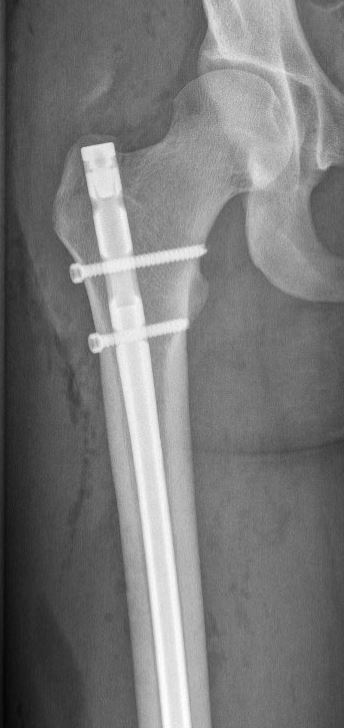

Veel gebruikt is een pen in de mergholte van het bot, die via de heup of via de knie kan worden ingebracht. De pen wordt vervolgens met dwarse schroefjes aan het begin en het einde van de pen vastgezet. Een andere optie is het gebruik van platen en schroeven om de verschillende breukdelen stevig aan elkaar vast te zetten. Voor het plaatsen van een plaat is wel een grotere snede nodig dan voor een pen. Indien er sprake is van een ernstig weke delen letsel en zeker als er meerdere ernstige letsels tegelijk aanwezig zijn, kan uw chirurg er ook voor kiezen om de breuk, al dan niet tijdelijk, van buitenaf vast te zetten met een extern fixatie mechanisme (de zogenaamde ‘externe fixateur’).